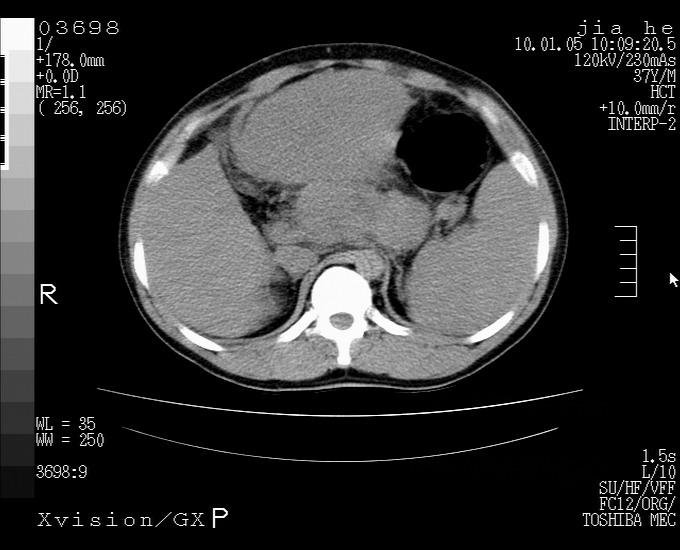

标题: CT23988:男,40岁,B超提示腹部肿物,请各位老师给看看。 [打印本页]

标题: CT23988:男,40岁,B超提示腹部肿物,请各位老师给看看。

左叶够大的,且与胰腺欠清晰,请增强扫描

肝左叶增大,建议增强扫描。

1.该患者有腹部手术史

2.脾大,肠系膜密度增高,有多发索条影,胰腺边缘毛糙,腹膜增厚,推测有肝硬化,门脉高压,腹膜炎和/或胰腺炎

3.肝左叶巨大站位,并腹腔淋巴结肿大,肝癌或肝间叶来源恶性肿瘤,也不排除大网膜间质瘤侵及肝左叶

建议:增强或磁共振

考虑肝左叶外侧段癌并腹膜后淋巴结转移.建议增强进一步检查.